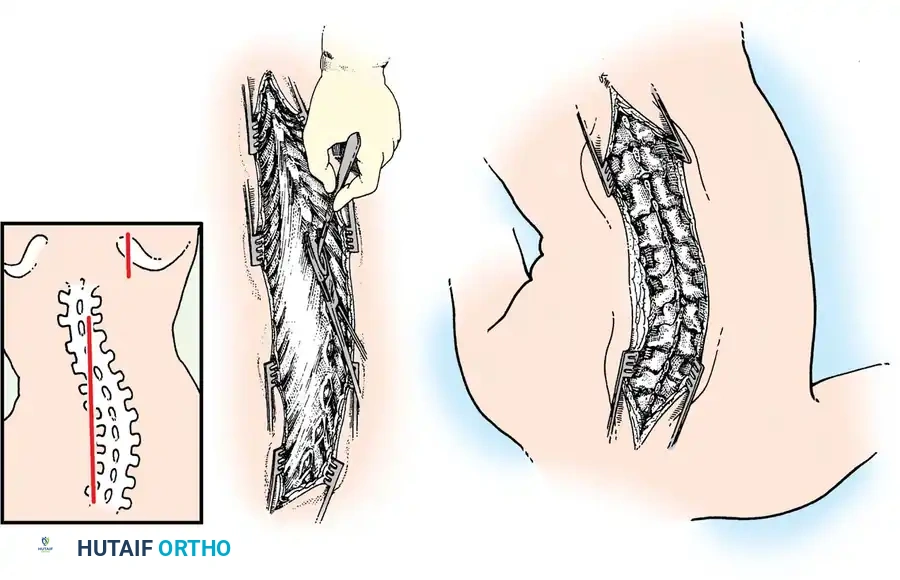

Fig. 38-23: A, Skin incisions for posterior fusion. B, Incisions over spinous processes and interspinous ligaments. C, Weitlaner retractors maintaining tension during dissection.

Incision and Superficial Dissection

- Skin Preparation: Scrub the patient’s back with a surgical chlorhexidine or iodine-based soap solution for 5 to 10 minutes, followed by an antiseptic paint. Drape the operative site widely and seal the skin with an antimicrobial plastic Steri-Drape.

- Incision Planning: Make a straight midline skin incision extending from one to two vertebrae superior to the proposed upper instrumented vertebra (UIV) down to one vertebra inferior to the lower instrumented vertebra (LIV). A perfectly straight scar significantly improves the postoperative cosmetic appearance.

- Hemostatic Infiltration: Make the initial incision through the dermal layer only. Infiltrate the intradermal and subcutaneous tissues with an epinephrine solution (1:500,000) to induce local vasoconstriction.

- Deepening the Wound: Deepen the incision through the subcutaneous fat to the level of the spinous processes. Utilize self-retaining Weitlaner retractors to maintain constant outward tension on the skin margins. Identify the avascular midline raphe (interspinous ligament), which typically appears as a distinct white line.

Deep Subperiosteal Dissection

- Cartilaginous Cap Incision: Incise the cartilaginous cap overlying the spinous processes precisely in the midline. Note that in severe scoliosis, the midline may be significantly deviated due to apical vertebral rotation.

- Cobb Elevation: Utilizing a Cobb elevator combined with electrocautery, expose the spinous processes subperiosteally. Move the cartilaginous caps and attached paraspinal muscles laterally.

- Direction of Dissection: It is anatomically advantageous to dissect from caudad to cephalad. The short rotator muscles (multifidus and rotatores) and ligaments of the spine attach obliquely, pointing superomedially. Sweeping upward works with the grain of these fibers, allowing for a cleaner, faster subperiosteal release.

- Maintaining Tension: As the exposure deepens, sequentially advance the Weitlaner or Cerebellar retractors. Constant, firm retraction is the surgeon's best tool for passive hemostasis.